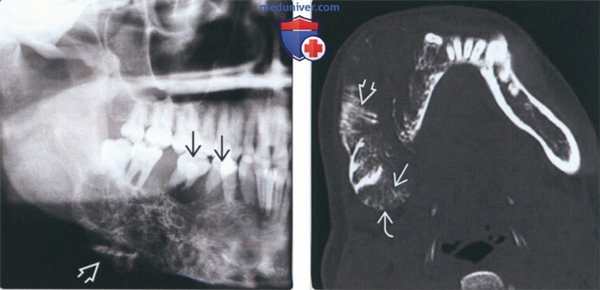

(Слева) На кадрированной панорамной рентгенограмме определяется большое многокамерное образование, смещающее зубы. Прямые перегородки в области вздутой нижней кортикальной пластинки создают «лучистую» картину псевдопериостальной реакции.

(Справа) На аксиальной КТ в костном окне у этого же пациента визуализируются прямые толстые перегородки и расходящиеся костные «пучки» на периферии опухоли. Тонкая краевая кортикальная пластинка помогает отличить одонтогенную миксому от остеосаркомы.